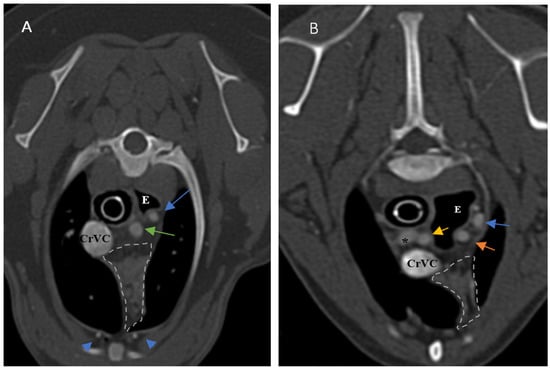

Figure 4. Demonstration of visibility and topographic location of grade 3 thymus. (A,B) are contrast-enhanced transverse sections of the thoracic region at the level of T2 and T3, respectively. (A): Five-month-old female Shih Tzu with a visible, homogenous, grade 3, rectangular-shaped and midline predominancy thymus with CT number equal to 93. (B): Four-month-old male mixed-breed dog with a visible, homogenous, grade 3, wedge-shaped and left-sided predominancy thymus with CT number equal to 90. Light grey dash lines illustrate the thymic borders. T: trachea, E: esophagus (which is dilated due to general anesthesia), CrVC: cranial vena cava, asterisk: right common carotid artery, hash sign: brachiocephalic trunk, arrows: left subclavian artery, and arrowheads: internal thoracic arteries.